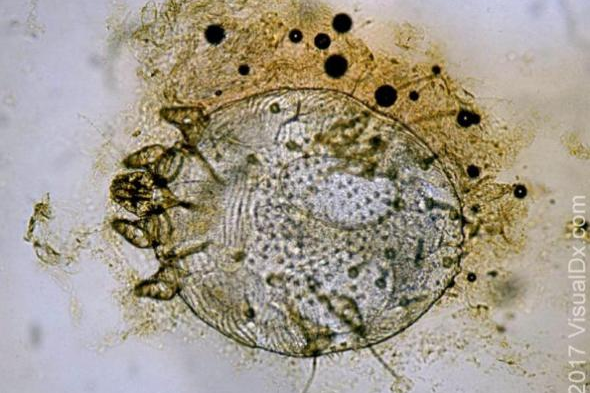

Scabies is a disease caused by Sarcoptes scabiei that takes up residence on the surface layer of the human skin. The skin is highly sensitive to this invasion, and as mites burrow into the skin and lay eggs, this disturbance leads to persistent rashes and itching.

Scabies mites are tiny, with adult bodies measuring about 0.3-0.5mm in length, ranging from milky white to brown, almost invisible to the naked eye, with four pairs of legs, male mites are slightly smaller, female mites are slightly larger, female mites are the primary causative agents (females tunnel and lay eggs in the skin, causing inflammatory reactions that lead to severe itching) .

The life cycle of scabies mites includes four stages: eggs, larvae, nymphs, and adults, all of which can be completed within the human skin, with a life cycle of about 2-3 weeks .

Female mites dig tunnels in the epidermis of the skin, lay eggs inside the tunnels, and after the eggs hatch, they develop into larvae, nymphs, and eventually adults. After mating, the male mites die, while female mites continue to dig tunnels and lay eggs, reproducing continuously.